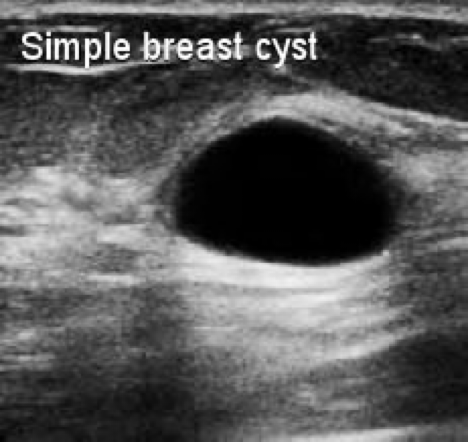

Acoustic enhancement:

- BecauseĀ ultrasound waves are hardly weakened in fluids, structures that are located behindĀ fluid-filledĀ spaces will appearĀ hyper-echoic shadow (brighter).

- Ultrasound is often used to Z **determine whether the structure is solid or cystic